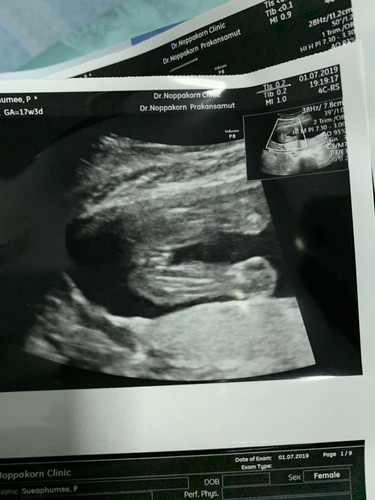

ผญค่ะ ในมุมขวามือล่างของภาพหมอระบุเพศไว้แล้วค่ะ

ล่างขวาสุด หมอระบุไว้แล้วค่ะ ว่าFemale คือผญ

ในรูปขึ้นว่า Female เพศหญิงคะ

ตรงด้านล่างที่เขียนว่า Female แปลว่าหญิงค่ะ

ขวามือล่างระบุFemale